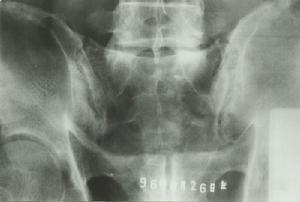

X線檢查早期常無特異性改變但後期可出現骶髂關節炎症。

X線正位片顯兩髂後上棘高低不等,斜位片可見骶髂關節間隙加寬,凸凹關係紊亂。